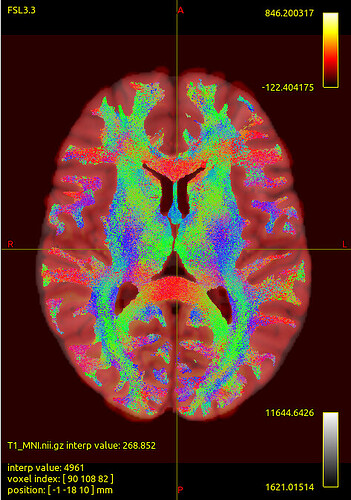

We noticed that the tck files already warped to MNI space are misaligned with the standard template in some sulcal and gyral regions. However, we also checked the registration between the T1 image and MNI space — even the T1 image warped to MNI space fails to align with the sulci and gyri of the MNI template. Nevertheless, the tck files in standard space show better alignment with the T1 image in MNI space. Can this be considered a good warping result? Figures are as follows.